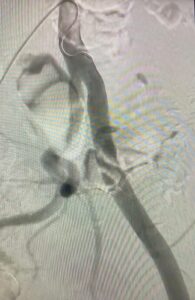

- Nuevo caso de endofibrosis ilíaca externa en ciclista profesional